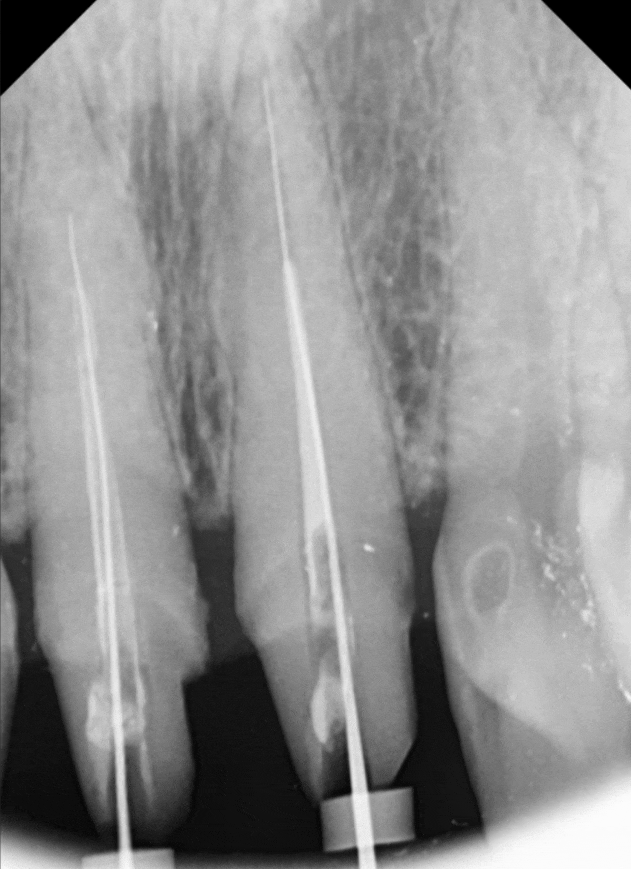

신경관 안에 딱딱하게 굳은

예전 재료를

치아 내벽 손상 없이

조심스럽게 걷어내야 합니다.

마치 좁은 터널 안에서

벽을 긁지 않고 작업하는 것과 같죠.

기존 치료가 불충분했다면

신경관이 막혀 있거나

방향이 뒤틀려 있을 수 있어,

원래의 길을 다시 찾아내는 게

정말 쉽지 않습니다.

230424

이번 환자분 역시 신경이

뿌리 끝까지 제거되지 않은 상태였지만,

다행히 숨은 길을 잘 찾아내어

3번의 꼼꼼한 소독 끝에

안전하게 치료를 마무리할 수 있었습니다.